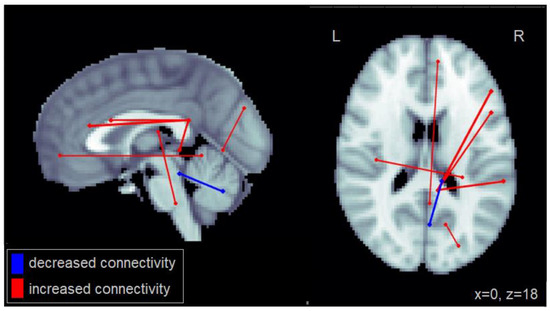

Similarly, increased steering variability (SD in steering) among patients with MCI was associated with increased connectivity between the right PCC and the right frontal gyrus as well as the right middle temporal cortex (Figure 3). Increased steering variability was also associated with reduced connectivity between cerebellar regions. This number of significantly reduced intra-cerebellar connections for steering variability was greater than that observed for lane deviations. Furthermore, increased steering variability was associated with reduced connectivity between the cerebellum and the middle and inferior temporal cortex. The complete set of regions showing alterations in connectivity among patients with MCI related to increased lane deviations is reported in Table A3.

Figure 3.

Altered functional connectivity associated with standard deviation in steering observed among patients with MCI. Blue lines denote functional connections with reduced connectivity associated with greater lane deviations, red lines denote increased connectivity (significant at FDR = 0.05). Connections are shown as projections in the sagittal and axial plane, with MNI anatomical underlays (slices at x = 0 and z = 18 respectively).